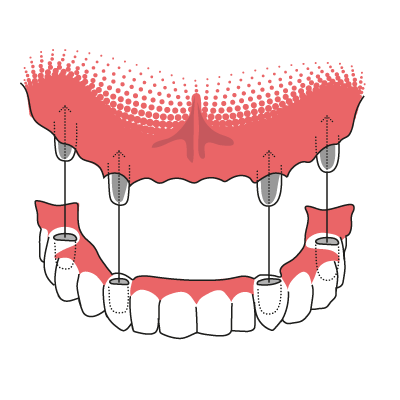

Stegprothese